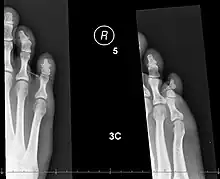

![]() | |

| X-rays of fractures of the proximal (left) and distal (right) phalanges in the little toe. | |